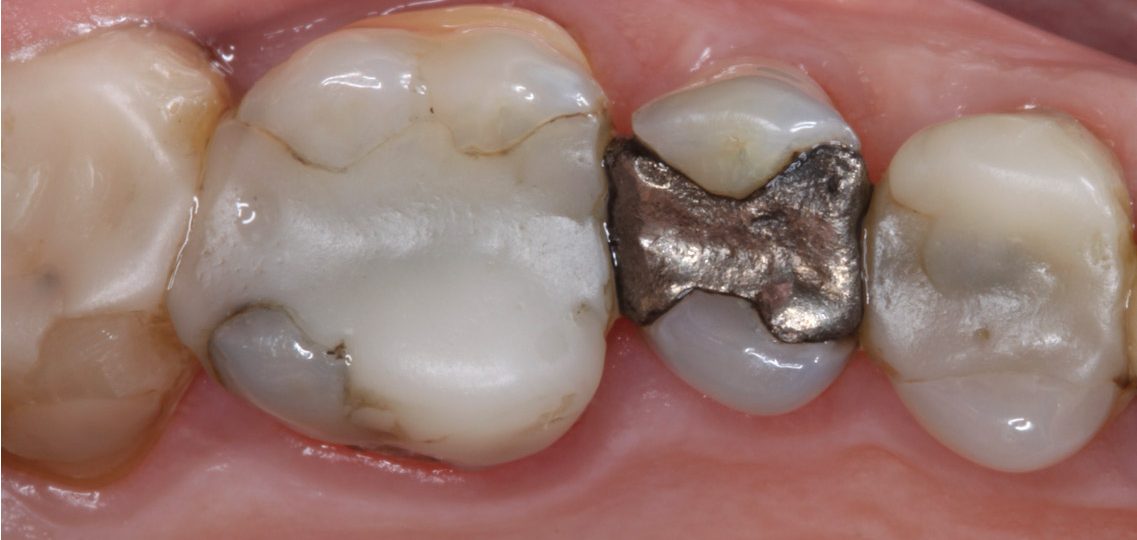

A heavily restored posterior dentition, with a history of fractures, may benefit from converting to canine guidance. This will also limit lateral forces on the weakened posterior teeth.

Patients in both of the photos below have heavily restored posterior dentitions. You could also make an argument that several cuspal coverage restorations are indicated.

However, if the patient did not consent to this, but wished to limit the risk of future fractures, then restoring the canines and ensuring canine guidance (for instance by canine rises in composite) would do this.